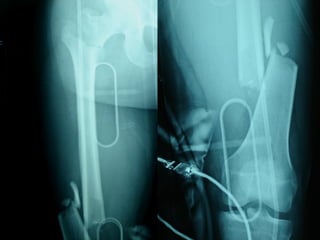

Dal Gennaio 2000 al Febbraio 2006 abbiamo trattato 167 fratture chiuse  con placca percutanea  in 164 pazienti :  27 lesioni diafisarie di gamba, 12 piloni tibiali ,  11 fratture prossimali di tibia, 36 fratture sovracondiloidee di femore, 17 fratture diafisarie di femore, 43 fratture metaepifisarie prossimali di omero, 21 diafisarie d’omero.  156 guarigioni 8 fallimenti

Dal Giugno 2002 al Dicembre 2004 abbiamo trattato 5 fratture esposte: 3 di tibia e 2 di ulna 5 guarigioni

I buoni risultati ottenuti dipendono da 5 punti fondamentali:   una accurata riduzione percutanea della frattura  precise vie di accesso  l’utilizzo della placca che consenta il più lungo braccio di leva possibile il pretensionamento della placca  una sintesi con un ridotto numero di viti

Fratture  esposte